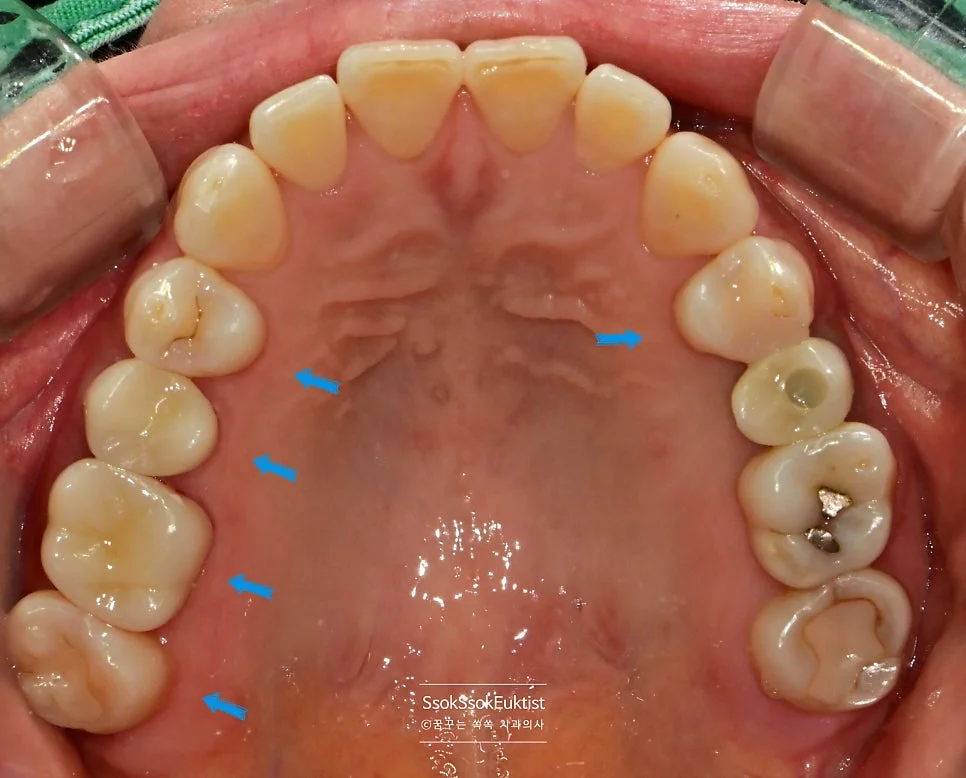

치료 전 구강 정면 — 겉으로는 큰 이상이 보이지 않지만 치아 사이에 충치가 숨어 있습니다

치아 사이를 가장 잘 볼 수 있는 교익 방사선(Bitewing X-ray) 사진을 통해 정확한 충치 진단을 시도합니다.

교익 방사선 사진을 촬영하였을 때, 치아의 가장 바깥 흰색 재질(법랑질)과 안쪽 회색 재질(상아질)을 나누는 선이 검은 음영으로 끊긴 느낌이면 충치로 진단합니다!

(위 사진에서 파란색 화살표로 표시된 부분)

구강 사진에서 하얀색 화살표는 충치의 위치를, 파란색 화살표로는 해당 치아를 번호로 기재하였는데요. 각 치아의 치료 계획에 대해 말씀드리겠습니다.